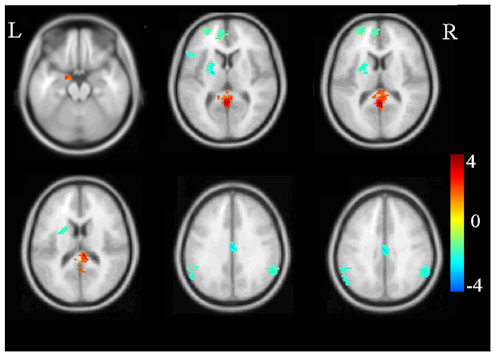

Although we do not use brain scans to diagnose PTSD in the clinic, we use them to understand what happens in the PTSD brain. There is abundant evidence for changes in the structure and function of different areas of brain involved in fear response and anxiety, regulation of emotions, cognitive processing and memory. For example, there is consistent evidence for reduced volume in the brain region called the hippocampus, which is involved in memory and context processing. This leads to difficulties differentiating cues that resemble trauma, such as the slamming of a door, from the trauma cue itself, such as a gunshot.

Abnormalities of the hippocampus also lead to impairments of differentiating a safe context from the context in which trauma happened. For example, this could be a fear response to road kill in Ann Arbor, Michigan, which may resemble an improvised explosive device (IED) in Iraq. We also know from fMRI research, the part of the brain called the amygdala, which is involved in fear response, shows larger activation in response to viewing or memory of trauma reminders, or viewing of negative facial affect. These findings are valid in studies averaging data across brain scans of dozens of people. They are not useful in a one-person diagnosis.

To summarize, brain imaging has been a very useful tool in understanding the aberrations in structure and function of a PTSD brain, but it does not diagnose the condition.